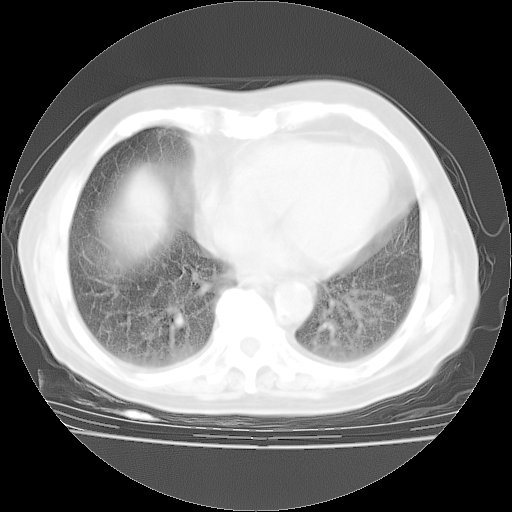

4月28日肺部CT——再次出现类似去年5月9日——透光度降低,“间质性”改变。

4月28日肺部CT——再次出现类似去年5月9日——磨玻璃样、间有“粟粒样”改变。

个人阅读4.14日肺部CT平扫:纵隔窗无异常,但肺窗示:双下肺内、后基底段有片絮状侵润影,部位以后基底段为著,以间质改变为主,呈急性肺泡炎征像,和首次住院影像学有相似之处。仅是个人读片,明日请相关专家再读片哈。其它建议同上。